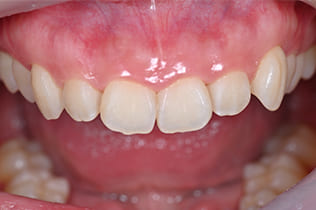

Case01

- 原因

- ガミースマイル

- 治療回数

- 1回

- 治療期間

- 術後治癒も含めて約1か月

- 治療内容

- ガミースマイル改善治療

- 治療費用

- 121,000円

(1ブロックあたり、6前歯部分)

笑った時に歯茎が見えてしまうガミースマイルを改善したいとのことでご来院された患者様です。術後も大変満足していただきました。